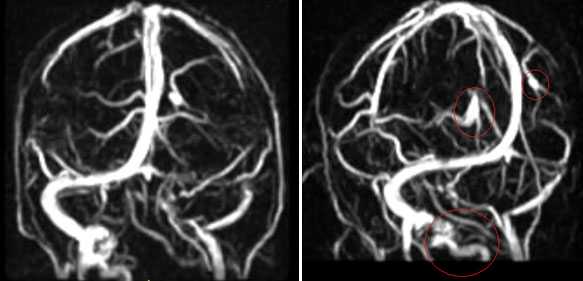

Тромбоз правого поперечного синуса - гипоинтенсивные участки по Т2 (внутриклеточный дезоксигемоглобин).

Для подтверждения тромбоза венозного синуса и определения точной локализации и протяженности тромба необходимо проведение МР-венографии.

МР-венография - отсутствие визуализации кровотока в правом поперечном синусе и яремной вене.

МР-венография: тромбоз правого поперечного синуса. Отмечается потеря МР-сигнала от правого поперечного синуса.

Наличие визуализации синуса на «сырых» данных или же МРТ головного мозга подтверждает тромбоз синуса и исключает его гипо- и аплазию.

Тромбоз правого поперечного синуса. Отсутствие феномена «пустоты потока» от правого поперечного синуса на МРТ головного мозга. Отсутствие визуализации правого поперечного синуса на МР-венографии.